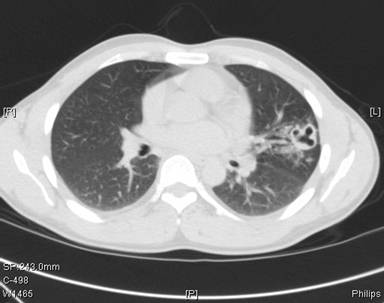

Fig 2: Chest computed tomography at presentation (4 months following initiation of antituberculous therapy)